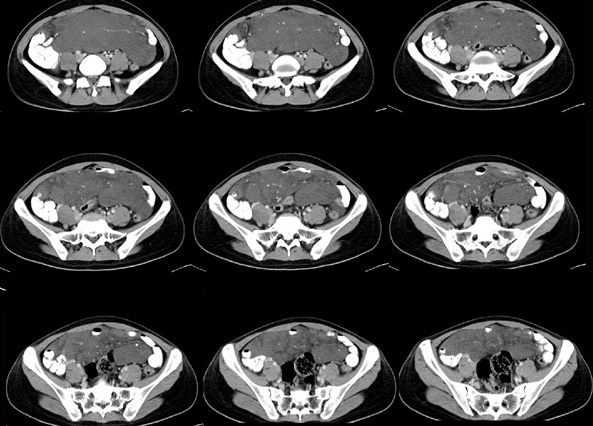

女性,28岁,停经3月,腹部膨隆1月,产前检查发现腹部占位

{肿块中心ct值27hu,增强后,动脉期、门脉期均无明显强化)

1 肠系膜肿块诸期无明显强化,肠系膜血管包绕其中但其周围仍见脂肪称“脂肪环征”;2 肠系膜血管远端较近端细,于重组像上见血管周围有强化结节为炎性结节,3肿块内见部分脂肪密度及少许点状钙化。4 腹膜后无肿大ln。

患者手术病理:腹腔囊性淋巴管瘤,象这样充满整个腹腔的的确很少见